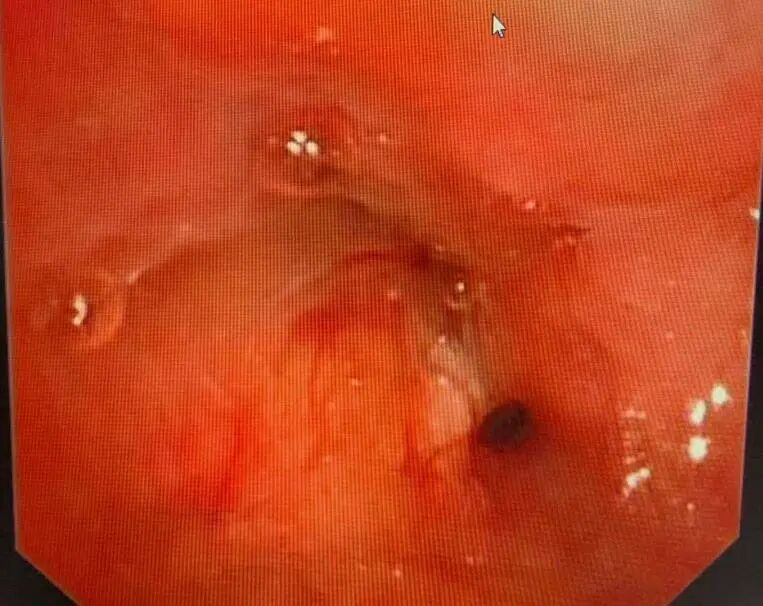

进一步的病理诊断结果明确:王叔患上的是鳞状细胞癌。气管镜检查下,能清晰看到左侧支气管管口被新生物堵塞,肿瘤牢牢“盘踞”在左上肺根部。如果贸然开刀,不仅要切除整个左肺,甚至可能因为肿瘤与血管、支气管粘连过紧,无法实现根治性切除,反而会给患者带来更大的创伤。

支气管镜下可见左上叶支气管口新生物